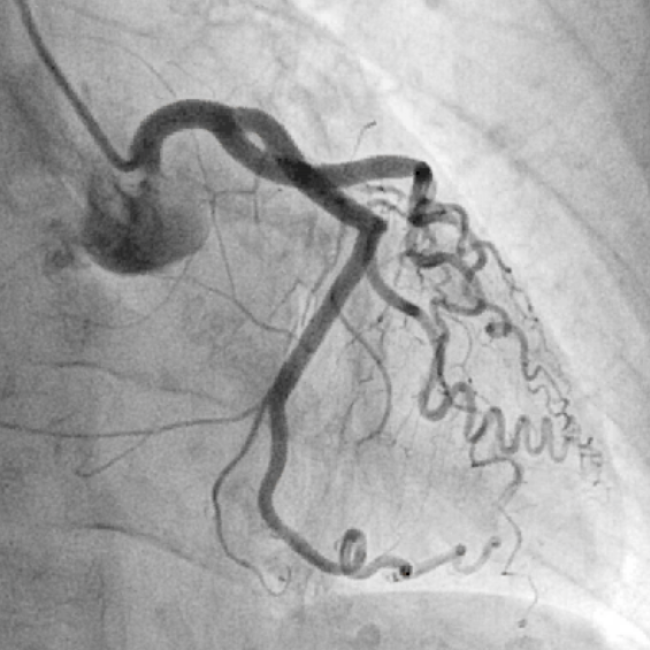

Existen diferentes tratamientos frente a un infarto de miocardio y una angina de pecho, entre los que se encuentran el cateterismo cardíaco, la angioplastia coronaria o el bypass coronario.